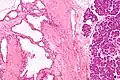

Pathologists classify serous cystic neoplasms into two broad groups. Those that are benign, that have not spread to other organs, are designated "serous cystadenoma".[5] Serous cystadenomas can be further sub-typed into microcystic, oligocystic (or macrocystic), solid, mixed serous-endocrine neoplasm, and VHL-associated serous cystic neoplasm. This latter classification scheme is useful because it highlights the range of appearances and the clinical associations of these neoplasms. Serous cystic neoplasms that have spread ("metastasized") to another organ are considered malignant and are designated "serous cystadenocarcinoma".

Pathology